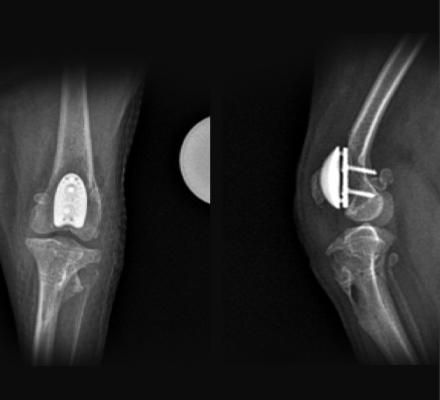

인공활차구 수술

관절 연골의 심각한 손상이 있는 환자에게 적용할 경우 환자에게 최선의 예후를 보장할 수 있습니다.

인공활차구(PGR)수술

“ 심각한 슬개대퇴연골 손상이 있는 경우

인공 활차구 수술로 환자의 불편함을 덜어줄 수 있습니다 ”

- 최신 수술 기술 PGR 도입으로 최신 검증된 맞춤 슬개골탈구 수술을 진행합니다.

- 기존 기술로 예후가 좋지 않을 수 있는 환자도 최선의 결과를 낼 수 있습니다.